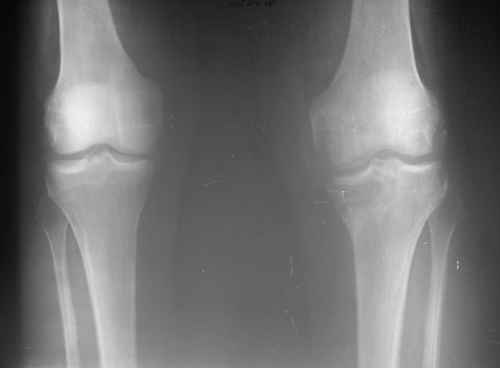

Мужчина, 54 г. Жалобы на ощущение неустойчивости и умеренные боли в левом коленном суставе, усиливающиеся при ходьбе, нарушение походки. Травму получил 8 месяцев назад - оступившись во время ходьбы, подвернул левую ногу в коленном суставе. Лечился гипсовой повязкой.Ходит при помощи трости.

вдогонку - качество снимка -не очень, но похоже на компрессию внутреннего плато большеберцовой кости. Не могу понять, что за деформация по внутренней поверхности внутреннего мыщелка бедра

Мне тоже кажеться , что имеет место перелом Медиального Мыщелка б\б кости.

Этим и обьясняеться и деформация проксимальной тибии и нестабильность.

скорее всего имел место перелом медиального мыщелка.КТ и артроскопия во-многом смогут помочь.Исходя из возраста и быстрого прогессирования артроза скорее всего потребуется вальгирующая остеотомия. Подобный случай, только с переломом латерального мыщелка у коллеги. я выкладывал на форум пару лет назад. После варизующей корригирующей остеотомии\ без ревизии КС\ я через год впервые увидел ее на конференции-рассекала на шпильках.Успехов Вам.